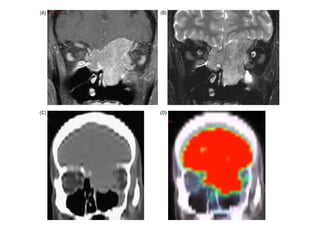

CT scans des sinus en coupe axiale (A) et coronale (B), avec injection de contraste :

Anévrysme trilobé du segment intra caverneux de l’ artère carotide interne droite

avec érosion paroi externe sinus sphénoidal.